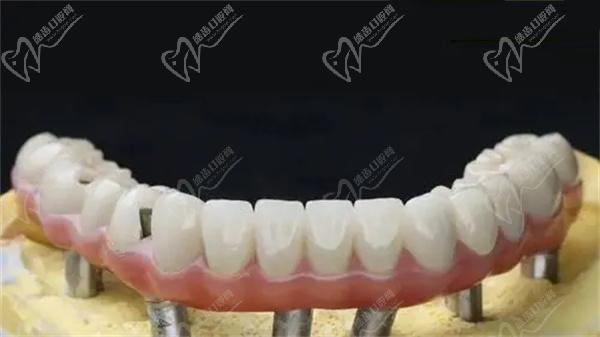

马龙桥(Malone Bracket)是由葡萄牙有名口腔种植牙名医 保罗·马龙(Paulo Malo)博士提出和发展的一种修复方案。其主要原理是在缺失牙齿部位安装一个“桥架”,然后将牙冠一个一个的安装上去,注意马龙桥牙的牙冠是独立存在的,如果有一个损坏只更换一个牙冠即可。但是all-on-4种植牙是安装4个植体,然后安装一个连接冠,如果其中一个牙冠损坏,需要更换连接冠。

马龙桥的特点是采用种植体植入牙龈和牙槽骨中,然后在种植体上连接人工牙齿,形成固定的“桥梁”,填补缺失的牙齿空隙。马龙桥手术通常需要在全麻下进行,手术的复杂性和费用较高,但它可以提供持久稳定的修复成效。

马龙桥的优点在于其适用范围广泛,可以用于各种复杂疑难牙齿种植等多种情况。同时,由于其植入方式简单,植入时间也较短,患者术后反应较轻。此外,马龙桥的使用寿命较长,患者更加舒适和方便地使用。

总结起来,马龙桥和All-on-4都是不错的牙齿修复技术,它们都可以恢复缺失的牙齿,提供良好的咀嚼功能和美观度。马龙桥采用6到8颗种植体,手术复杂耗时长,适用于不同种植情况的患者;而All-on-4只使用4颗种植体,手术简化,适用于牙槽骨密度较低的患者。选择合适的治疗方案应该根据患者的具体情况来综合考虑,与正规口腔医生进行详细咨询和讨论。